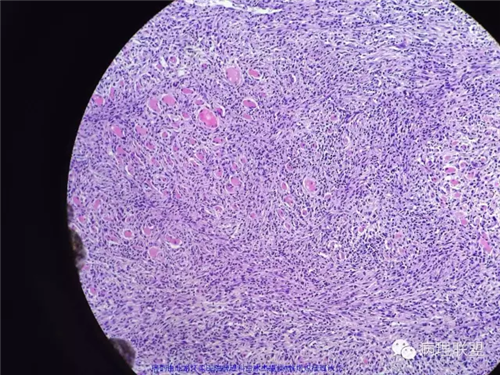

甲状腺肿物,镜下梭形细胞肿瘤,伴坏死及钙化,侵犯横纹肌及涎腺,不知道各位老师考虑什么,免疫组化还没有方向,低分化恶性梭形细胞肿瘤?炎性肌纤维母细胞肿瘤?甲状腺原发还是涎腺原发?谢谢。

好吧 俺也瞎叨叨几句:1,这一例的关键是确定和甲状腺的关系。虽然大体以及描述都说的是甲状腺,但图中没示任何甲状腺。如果找到正常甲状腺组织,当然可以;如果找到其他甲状腺高分化癌的成分,也有提示意义,2,临床表现,80岁,先倾向于UTC了;如果生长再迅速一点,那更支持了。3.镜下,UTC的几个特点(i) widely invasive growth, (ii) extensive tumor necrosis, (iii) marked nuclear pleomorphism, and (iv) high mitotic activity. 此处的坏死,是geographic coagulative necrosis,所以俺才说是有特点。